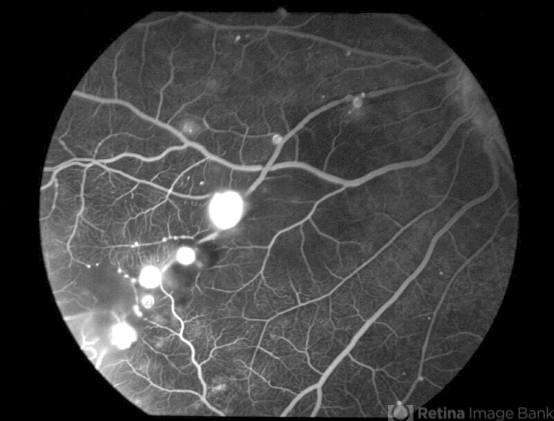

- Fundus fluorescein angiogram of the nasal quadrant of the active left eye of a 26-year-old female with bilateral LMA.